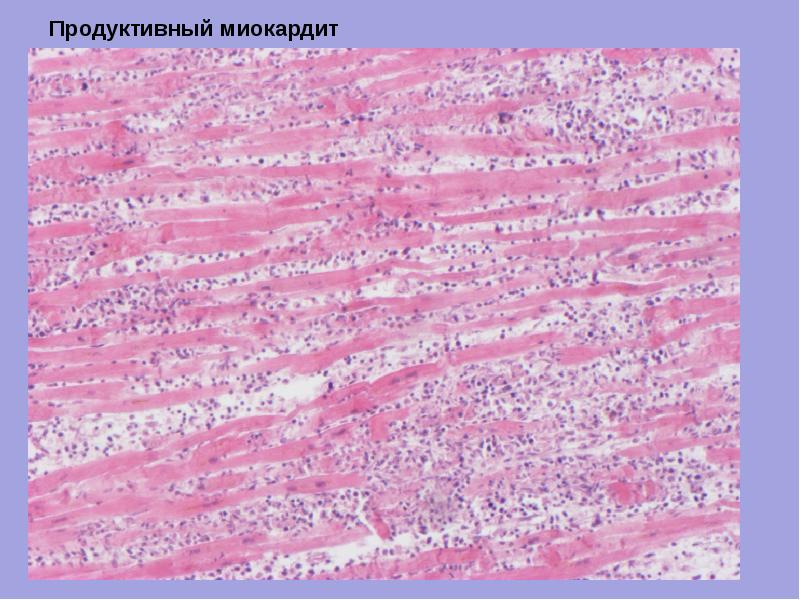

Межуточный миокардит: гистологические исследования

Раздел: Идеи и советы